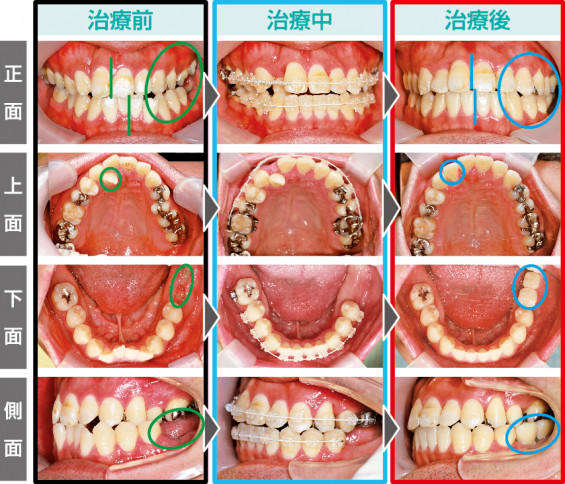

No.138 不正咬合と大臼歯欠損を伴った包括的矯正治療

2021/09/19今回の患者様は27歳男性の方で、臼歯部交叉咬合のため、噛み合わせが左側にズレており、さらに下顎左側の大臼歯2本と下顎右側の大臼歯1本が欠損しているため、咀嚼機能を回復させるために矯正治療を開始することとなりました。

まずは、交叉咬合を改善すべく歯列を広げる拡大装置を口蓋に装着しました。

さらに右上2番が内側に完全に倒れ込んでいたため、マルチブラケットにてスペースを確保しながら並べていきました。

約2年間でしっかり咀嚼できる機能的な歯並びになったところで、左側臼歯部に2本のインプラントを埋入しました。右側臼歯部も1本欠損していますが、ここにはインプラントを埋入せず現状維持でいくこととしました。

天然歯における不正な歯並びには歯列矯正を行い、歯を失った箇所にはインプラント治療を行うことで、機能性に優れた咬合状態へと回復させてあげられます。